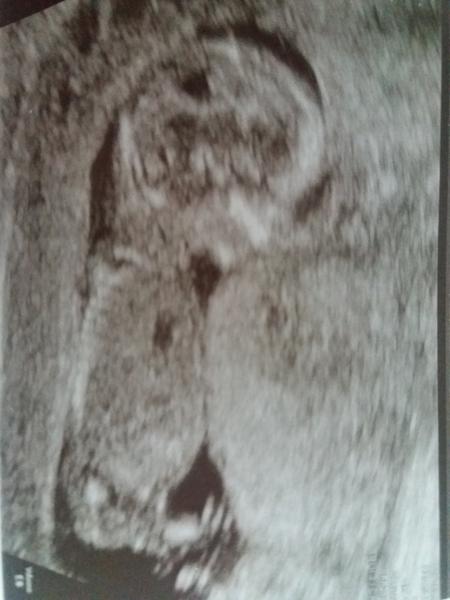

Přikládám foto ultrazvuku holčičky v 16tt pro ostatní maminky pro porovnani, je to zaber zespodu jakoby na prdku s roztazenyma nozkama 😉.

@fiendish.angel pokud je to za nožičkou pohlaví hrbolek tak by to měla týt holčička

@kristyna14092013 holčička. pohlavní hrbolek je souběžně s osou páteře. kdydy výrazně čněl nahoru, je to kluk 🙂